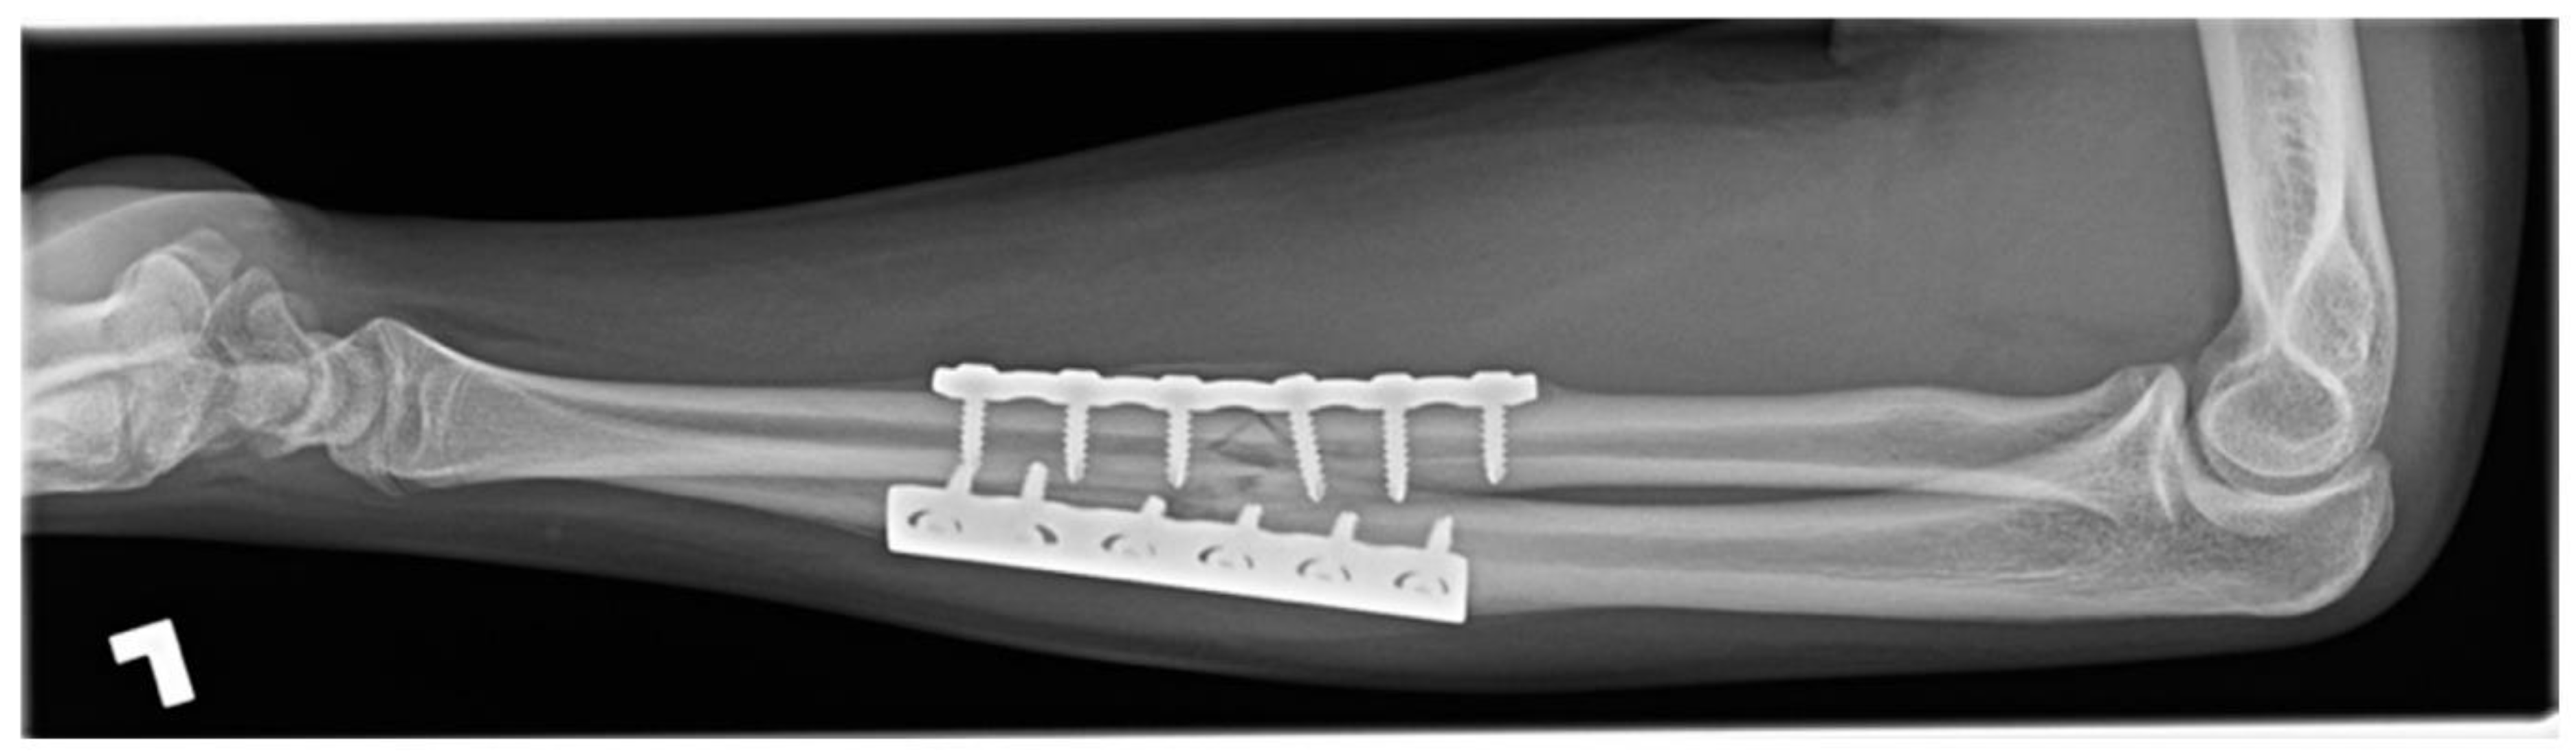

1.3. Forearm Fracture on a Trampoline, Eighteen Weeks in a 15-Year-Old Male

A fifteen-year-old male sustained closed, neurovascularly intact, displaced fractures of the radial and ulnar diaphyses with comminution of the radius. The mechanism of injury was a fall on an outstretched hand on a trampoline. The patient had no systemic comorbidity and no history of smoking but was a current user of electronic cigarettes. The fracture was splinted in a peripheral Emergency Room and was referred to our centre. The following day, the fractures were definitively treated without complication by open reduction internal fixation (ORIF) with plates and screws. The simple ulnar fracture was plated in compression mode, and the mildly comminuted radial fracture was approximated and plated in bridge mode.

Five weeks after operative treatment splint immobilization was discontinued, and a functional brace was applied. Eight weeks after ORIF, radiographs demonstrated bony union of the ulna but no union of the radius fracture despite anatomic alignment. The patient was counselled to discontinue EC use. Again, at twelve weeks, there was no union of the radius fracture and the patient had ongoing symptoms (Figure 3). Delayed union was diagnosed. Eighteen weeks after ORIF the patient had clinically improved, radiographs demonstrated bony union, and treatment was discontinued.

Figure 3.

Twelve-week radiograph of an operatively treated both-bones forearm fracture in a pediatric electronic cigarette user. The ulna is healed, but the radius is not.